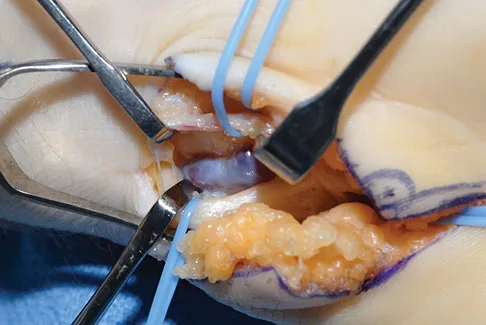

A 50-year-old man with metastatic renal cell carcinoma has right hip pain. A radiograph and CT scan are shown in Figures 48a and 48b. The first step in management should consist of

Explanation